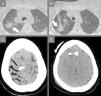

(A) Chest CT prior biopsy. The white arrow indicates the target lesion in the right upper lobe, in close proximity to the main fissure. (B) Chest CT during the biopsy. An 18-gauge Tru-Cut needle is successfully advanced through the target nodule under continuous CT-fluoroscopy guidance, as indicated by the white arrow. (C) Brain CT 19min after the biopsy. The white arrows indicate air in the right superior frontal, precentral, central (A) and superior temporal (B) sulci, consistent with cerebral venous air embolism. (D) Brain CT 3 days after biopsy showing complete resorption of the air bubbles. The white arrowhead indicates the external ventricular derivation.

After obtaining the informed consent and under local anesthesia, an 18-gauge Tru-Cut core biopsy needle (Argon Medical Devices, USA) was inserted under fluoroscopy-CT guidance through the right pectoral muscles. A specimen of the lesion was collected in a single shot (Fig. 1B). Immediately after needle removal, the patient experienced hemoptysis and had a tonic–clonic seizure. According to the abovementioned algorithm, the cardiac arrest team was called, 100% oxygen supply was started and both chest and brain CT were performed, 19min after lung puncture. The brain CT showed mild cerebral edema and the presence of bilateral intracranial air, mainly located in the right frontal and parietal lobes, suggesting SAE (Fig. 1C). The patient was then moved to the right lateral decubitus and high flow oxygen was continued during its transfer to the intensive care unit. Neurological assessment scored 8 points in the Glasgow Coma Scale (Eyes=2, Verbal=2, Motor=4), which prompted the placement of an external ventricular derivation to control the intracranial pressure. A drug-induced coma was maintained for 48h. Upon awakening, the patient's vitals normalized, and the neurological deficits improved. The brain CT performed 3 days after the biopsy, showed complete resorption of the cerebral air bubbles and normal permeability of the main intracranial venous sinuses. She was discharged 10 days later, after complete recovery.